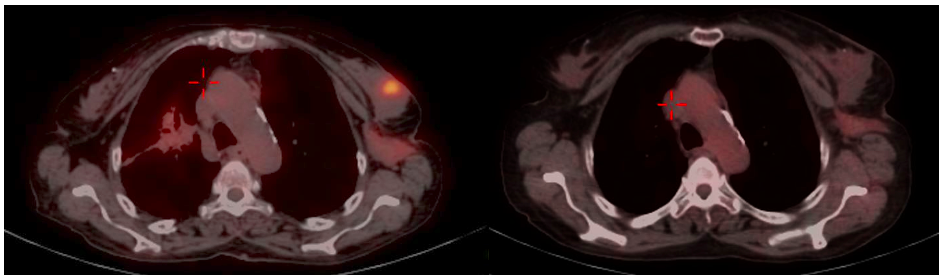

Mammography (Figure 1)revealed a large, round, well circumscribed, high density mass in upper outer quadrant and central region, measuring 7 x 6 cm. No suspicious calcification, architectural distortion, nipple retraction, skin or nipple-areolar thickening was seen. Associated was a large node measuring 11 x 9 cm noted in the left axillary region. Right breast and axilla were unremarkable. Correlation USG images were not available on Electronic Medical Record and PACS system, hence not available for reproduction here, however, as per the report, it appeared as a lobulated hypoechoic mass in left breast with necrotic changes, and internal vascularity in the solid component. Similar morphology additional left axillary mass was also seen. Imaging features highlighted the absence of spiculation, calcification, architectural distortion, irregular margins. The mass was categorized as BIRADS 4c, with a high probability of malignancy.Differentials on basis of mammography and USG were triple negative breast carcinoma, phyllodes tumor, cellular fibroepithelial lesion, organized abscess, lymphoma or metastases. CT was done to see disease extent which revealed a heterogeneously enhancing left breast mass (Fig 2a), large axillary and retropectoral adenopathy. No other adenopathy or abnormality seen. Biopsy from the breast lump was performed which showed Non-Hodgkin’s lymphoma of diffuse large B cell type, positive for CD20 and Mum1 which are markers of mature B cells. CSF study and Bone marrow aspiration were negative for involvement by disease. Diagnosis of primary breast lymphoma was made and planned for chemotherapy R-CEOP (rituximab, cyclophosphamide, etoposide, vincristine and prednisone) followed by IFRT (Involved field radiotherapy). Post 3 cycles of chemotherapy, FDG PET (Fig 2b and 3a) was done which showed significant reduction in size of breast mass and axillary node, breast mass then measuring 2 x 2cm with SUVmax of 7 while the axillary node measured 3.4 x 2.6 cm with SUV max of 3.7. Another repeat FDG PET Scan (Fig 2c and 3b)was done after completion of chemotherapy for further response assessment which showed no FDG uptake in left breast lesion suggesting complete metabolic response however size of the lesion appeared nearly stable, as compared to previous FDG PET (performed in the interim period of therapy). Patient has a 2-year disease free interval, and has not visited due to the Covid pandemic situation, but on telephonic follow up, is asymptomatic with good performance status. Figure 4: Low power (a), High power (b) and CD20 staining (c) from another case of primary breast lymphoma. These are representative images added here for teaching purpose. Figure 2a (10x power) shows diffuse infiltration by malignant cells. Figure 2b shows monomorphic round cells with apoptosis. Figure 2c staining positive for phenotype analysis for B cells. Representative USG image (Figure 5 and 6) of different patients with biopsy proven B cell lymphoma with different demographics. (Figure 5) USG of breast lump in a 56 year old woman shows hypoechoic, round mass, circumscribed margin with posterior acoustic enhancement mimicking a receptor negative carcinoma, mucinous carcinoma or fibroepithelial lesion. (Fig 6) Large mass in a 21 years old lady shows mixed echogenicity oval mass of parallel orientation, with well circumscribed margin and surrounding echogenic rim due to edema, mimicking a phylloides tumour, a fibroepithelial lesion or a malignant etiology.